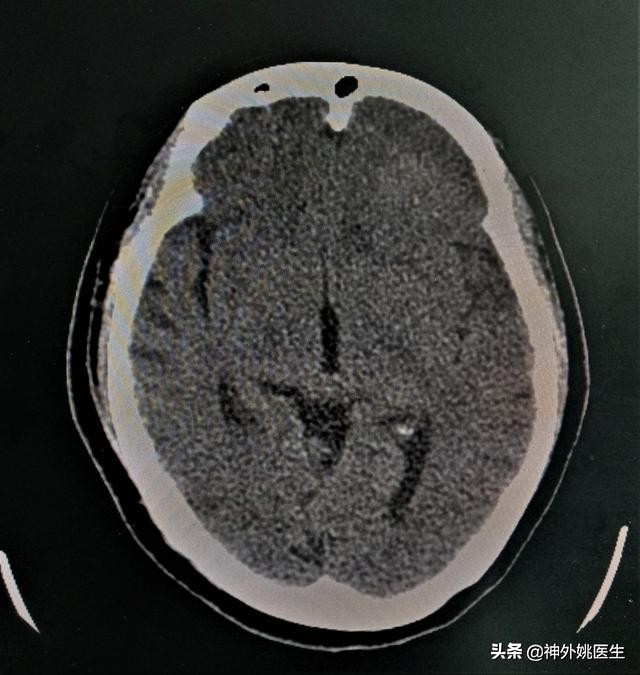

头CT检查:左额部占位,考虑脑膜瘤。(图1、2)

图1 左额部可见类圆形等密度影,大小约3.6cm x 3.9cm。